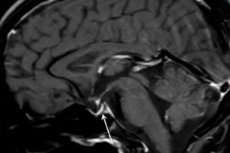

Инструментальная диагностика – с использованием компьютерной томографии (КТ) или магнитно-резонансной томографии (МРТ) головного мозга – позволяет исследовать размер и структуру гипофиза. На ранних стадиях гипофиз расширен, с течение времени железа атрофируется, и развивается такой выявляемый при сканировании диагностический признак патологии, как «пустое турецкое седло», то есть отсутствие гипофиза в гипофизарной костной ямке у основания мозга.